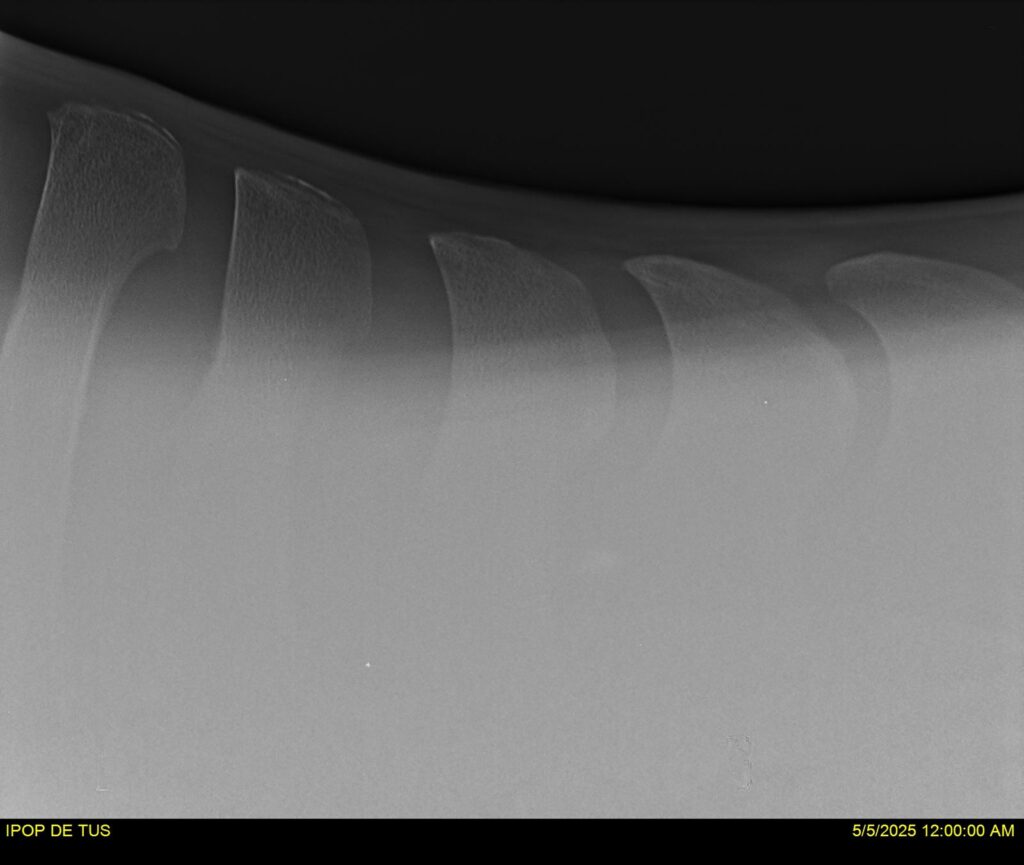

IPOP DE TUS, selle français, hongre, prendra 8 ans en 2026. LIFESTYLE x EROTICBLUS MONTOIS. Sans faute sur 125 et 130. Gentil cheval, respectueux avec des moyens et de la force. Transport OK, maréchalerie OK (pieds nus), santé RAS, Bilan clichés radios + clinique OK.

RADIOS ET CLINIQUE